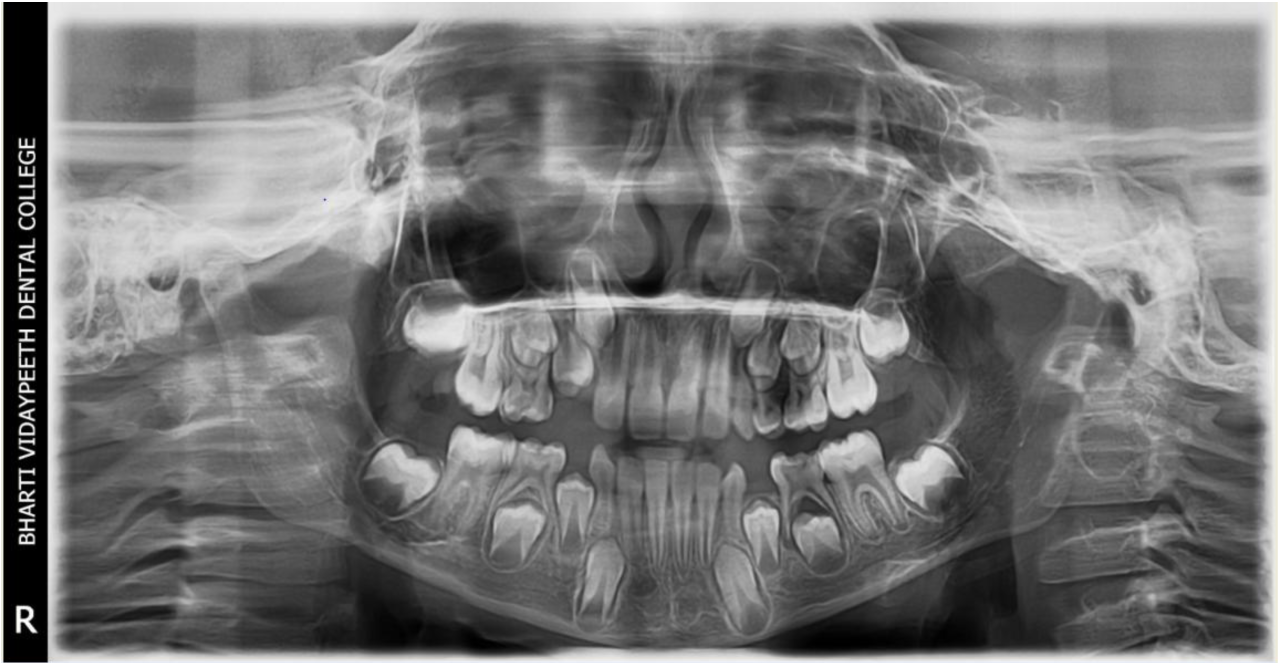

A nine year old boy reported to the Department of Pedodontics and Preventive Dentistry of Bharati Vidyapeeth Deemed University, Sangli with a chief complaint of pain and abscess in the lower left back region of the jaw since one month. Patient was a known case of autism spectrum disorder. He was inattentive, hyperactive and showed repetition of gestures. Psychological testing report showed childhood autism rating scale (CARS) 2, which falls into mild to moderate autistic category. Vineland social maturity scale (VSMS) measuring the social intelligence of child was found to be 31.5 with social age of around 5-6years. The family history was non-contributory. He was not on any medications and had reported no history of drug allergies. Extra-oral examination showed no specific findings (Figure 1). Intraoral examination revealed multiple carious lesions (Figure 2) (Figure 3). Occlusal caries involving enamel, dentin and pulp with 55 and 75. Intra oral dentoalveolar abscess was also seen in relation with 75 (Figure 4). Dentinal caries was seen with 85 and occlusal pit and fissure caries was seen with 65. No soft tissue abnormalities were appreciated. Radiographic evaluation by orthopantomogram was also done which revealed no abnormality (Figure 5). It was difficult for the patient to co-operate on the dental chair and understand the instructions given to him; hence treatment was planned under general anaesthesia. A complete pre anaesthetic evaluation was done and the patient was categorized under ASA II. Treatment plan was explained to the child’s parents and a written consent was obtained from them. The dental treatment done under general anaesthesia included pulpectomy of 55, 75 with glass ionomer cement restoration followed by placement of pre trimmed and pre contoured stainless steel crowns (Figure 6) (Figure 7). Glass ionomer cement restorations were done in 65 and 85 and pit and fissure sealants application on 16, 26, 36 and 46. Post-operative orthopantomogram showed well placed restorations and crowns (Figure 8). Patient’s post-operative recovery was uneventful. Treatment rendered reduced the pain and discomfort.Oral hygiene care instructions were given to the parents and maintenance protocol was explained and they were also encouraged for regular follow-up for preventive dental care. The two months follow-up revealed improved eating habits of the child.

Figure 5 Pre-operative orthopantomograph.

Figure 8 Post- operative orthopantomograph.